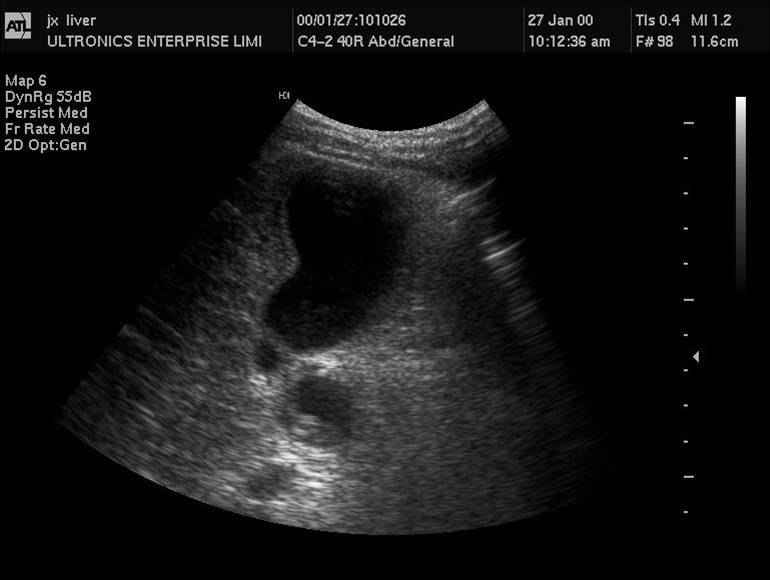

1 胆管结石